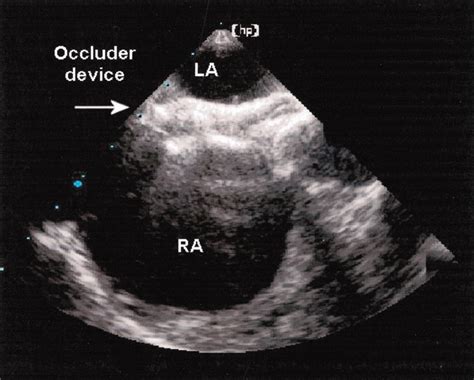

• Tee Echo Procedure

• Tee Heart Procedure

• Tee Ultrasound Probe

• Tee Medical Procedure